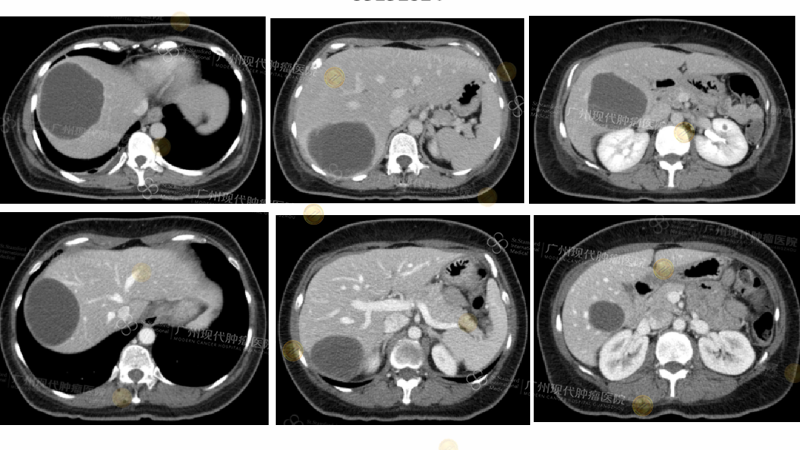

This 48-year-old patient with ovarian stromal sarcoma had metastasized to most of her liver and both lungs after failing multiple lines of chemotherapy. Precision diagnosis showed high expression of VEGFR2, FGFR3, and c-MET in her tumors, accompanied by significant biological dysfunction. Following a combination of biotherapy, targeted drugs, and supportive care, the patient's tumor rapidly shrank and she entered remission.

(CT shows complete disappearance of the tumor lesion)